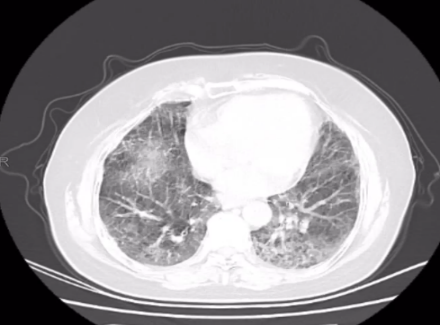

11月18日胸部 CT:双肺新发弥漫磨玻璃影,纤维化较前加重。

CT 影像:11 月 27 日复查胸部 CT,可见双肺磨玻璃渗出影明显吸收,对比 11 月 18 日影像,肺部病变改善显著。

11月18日肺部 CT

患者肺部影像学提示双肺间质纤维化伴磨玻璃样渗出影,考虑慢性纤维化性间质性肺病伴急性感染,患者高龄、免疫低下,给予呼吸支持的同时积极抗细菌、抗机会性感染。入院时血气提示I型呼吸衰竭,结合影像表现符合急性呼吸窘迫综合征,在基础治疗的同时应积极对抗全身炎症反应,西维来司他钠作为核心抗炎抗纤维化药物,它的应用是本次治疗的关键。其独特机制可针对性抑制肺部炎症反应和纤维化进展,与尼达尼布存在协同作用。避免了长期大剂量激素带来的血糖升高、感染风险增加等不良反应,符合当前间质性肺病治疗中 “减少激素依赖” 的趋势。从治疗效果来看,患者炎症指标快速下降、肺部病变显著吸收,证实了该药物在慢性纤维化性间质性肺病急性加重中的重要作用,尤其适用于非感染性炎症主导的病情进展。但西维来司他钠与尼达尼布联合使用的协同机制尚需更深入的基础研究验证,是否可根据患者具体表型调整剂量或用药时长,以达到更优治疗效果仍需讨论。